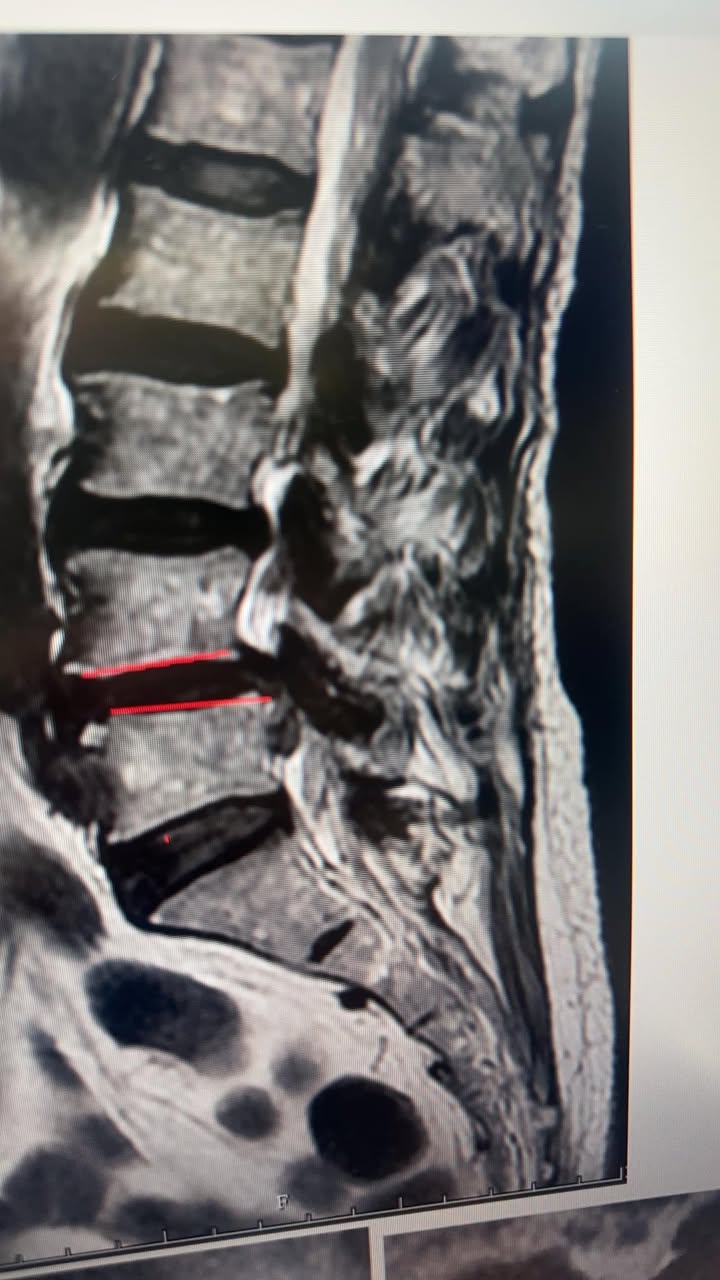

今天一個從台中上來治療的老媽媽患者!印象中治療今天第四次,改善超多,在診間跟我鞠躬🙇♀️道謝,害我很不好意思,連忙去扶她起來,我還跟她鞠躬謝謝她那麼信任我,原本過年前來診前已經痛到子女如同熱鍋上的螞蟻,圖片是當事人的核磁共振,嚴重椎管狹窄合併滑脫,原本都要去開刀了,孝順的子女親自帶媽媽北上,過年前那個時候只有一個禮拜的時間連續密集治療三次!然後就等待我回國,沒想到今天看到她她整個表情完全不一樣,改善非常多,讓她可以安心的過年她很開心!小孩更開心